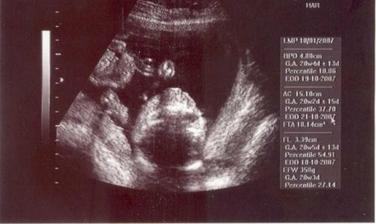

Na svet by som mala prísť 17.10.2007, budem sa volať Emka (v prípade, že sa pani doktorka pomýlila, tak Palinko) a maminka s tatinkom sa na mňa stráááášne tešia!

Narodila som sa 19.10.2007 o 00.45, som naozaj Emka, pri narodení som vážila 3400 g a merala som 49 cm. A som to najkrajšie bábätko na svete 🙂